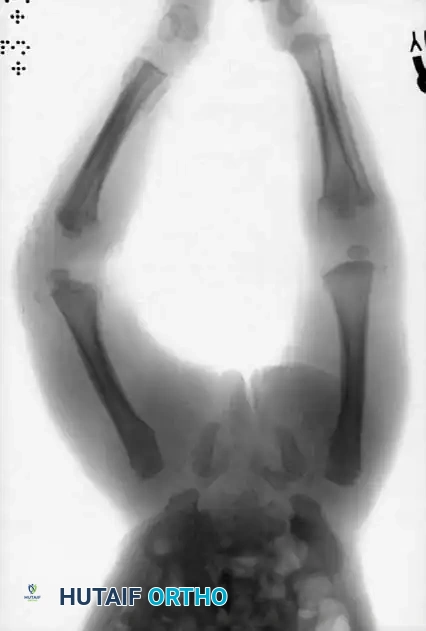

3. Posterior Rib Fractures: Caused by aggressive squeezing of the infant's thorax.

4. Complex Skull Fractures: Especially those crossing suture lines.

Image

Pathognomonic Clinical Findings:

* Multiple areas of large ecchymoses in different stages of resolution (ranging from black and blue to brown and green).

* Associated non-orthopedic injuries: skin burns (cigarette burns, immersion burns), ocular changes (retinal hemorrhages indicative of shaken baby syndrome), hematuria, and intra-abdominal injuries.